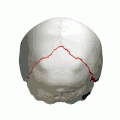

Animation. Lambdoid suture shown in red.